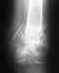

Разрезали локоть , поставили спицы, проволоку. на снимке после операции, видно что отломанная косточка не плотно прилегает к основной кости. Подскажите пожалуйста чем это чревато? И в Целом что вы думаете об установленных спицах и прогноз - будет ли работать сустав без ограничений( движение и нагрузки)? наложен гипс, меняют повязки на ране сейчас через день, Но спустя 11 дней после операции, отечная кисть, за ночь отечность спадает, но пока езжу на перевязку, и домой, то отек опять сильно увеличивается, это так и должно быть?